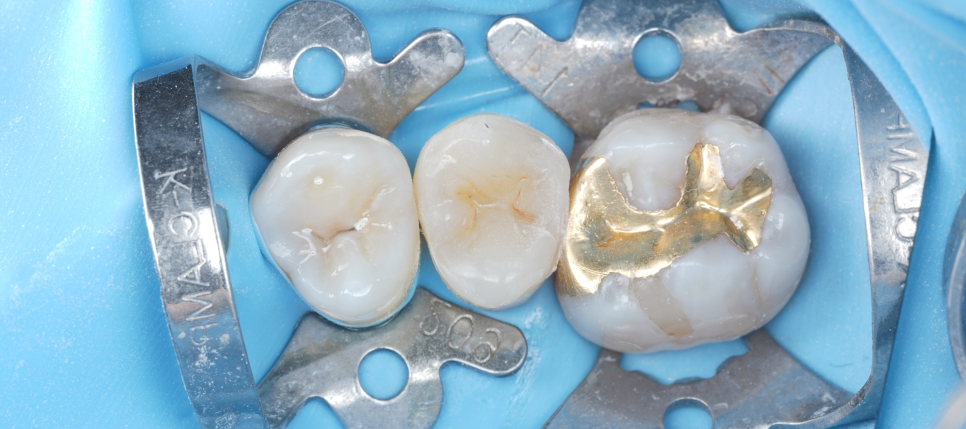

내원하셔서 확인해 보니 오른쪽 위 작은 어금니는 이미 신경치료가 끝난 상태였고 안은 임시 재료로 막혀 있었습니다.

촬영일 : 251124

교합면(씹는 면)은 이미 어느 정도 삭제가 되어 있었지만 나머지는 어느 정도 남아 있는 상태더라고요.

그래서 이런 판단을 했습니다. '굳이 더 깎을 필요는 없겠다. 이 정도면 레진 빌드업으로 충분히 살릴 수 있겠다.'